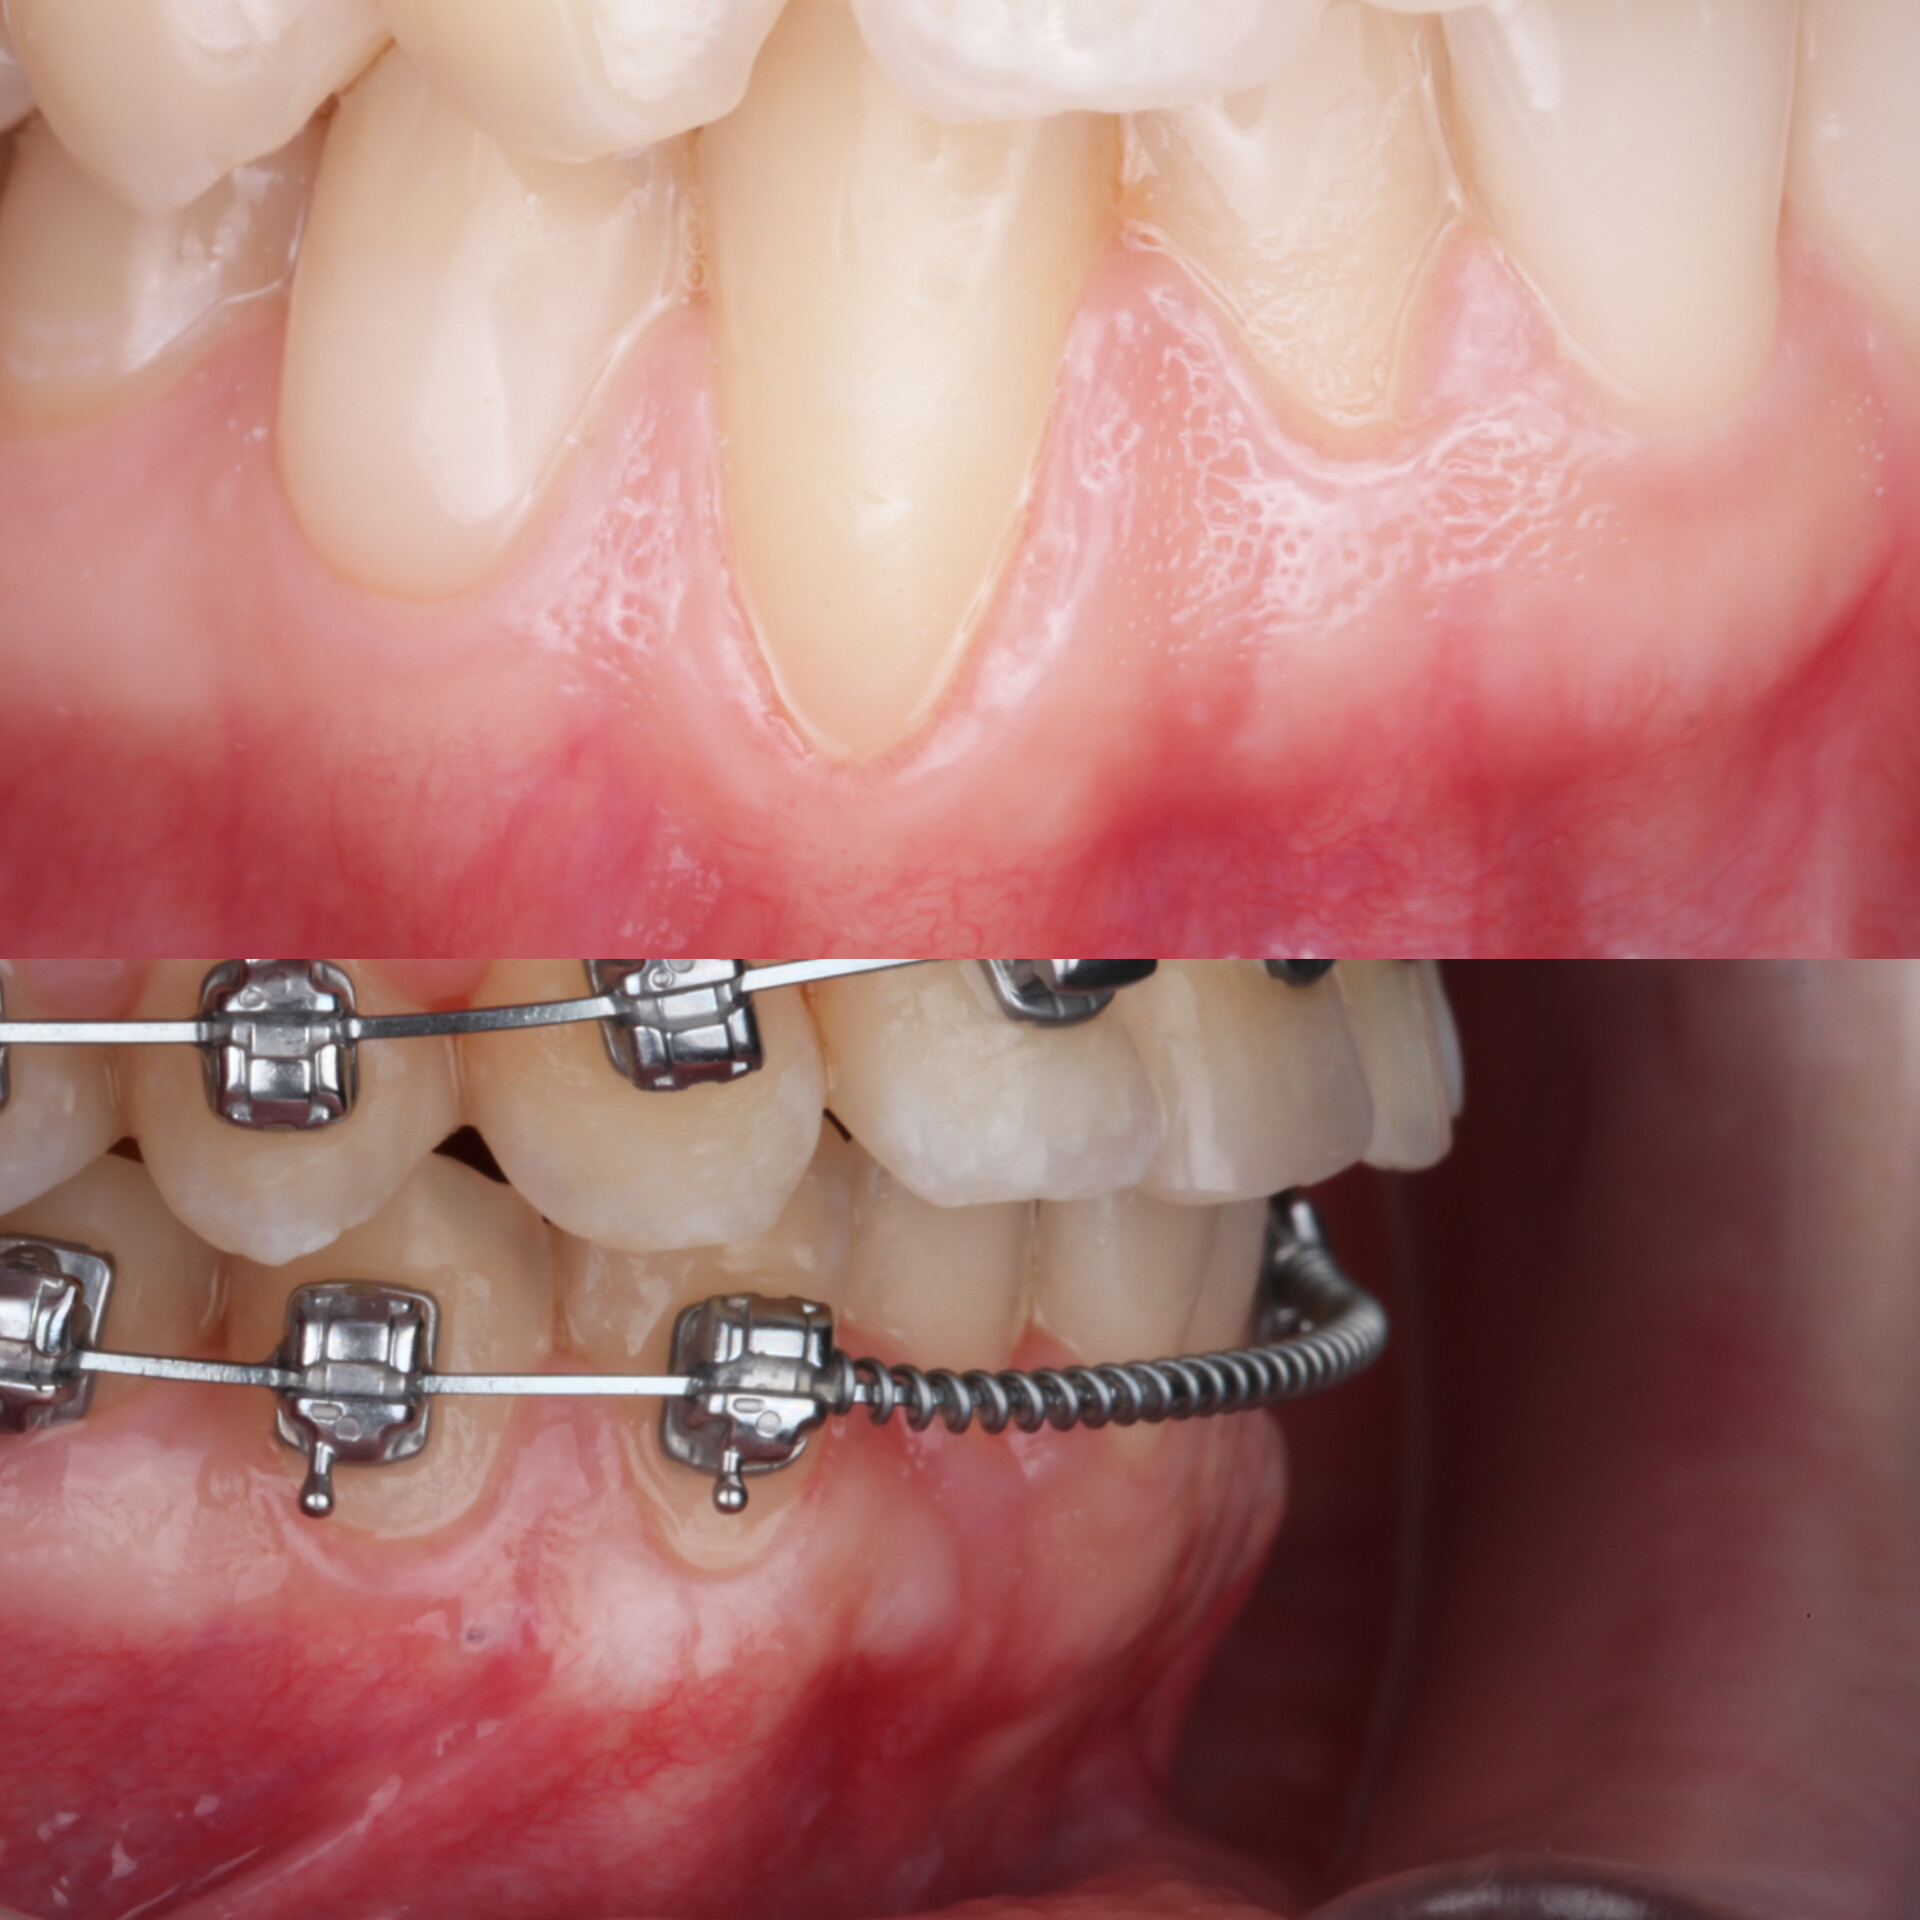

Спустя два месяца ортодонт зафиксировал брекеты. Мы видим полное закрытие рецессий и увеличение толщины десны. Это делает ортодонтическое лечение безопасным, а вероятность возникновения рецессий десны в дальнейшем — минимальной или практически невозможной

Осмотр спустя 6 месяцев :

Мы видим полное закрытие рецессий, увеличение толщины десны, что в дальнейшем делают ортодонтию безопасной, вероятность возникновения рецессий десны в дальнейшем минимальным или практически невозможным.